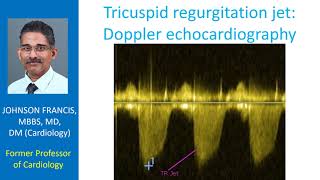

The Appearance of Mitral Regurgitation Tricuspid regurgitation jet – Doppler echocardiography

Tricuspid regurgitation jet – Doppler echocardiography Tricuspid regurgitation: symptoms, causes and treatment | Animation

Tricuspid regurgitation jet – Doppler echocardiography Tricuspid regurgitation: symptoms, causes and treatment | Animation